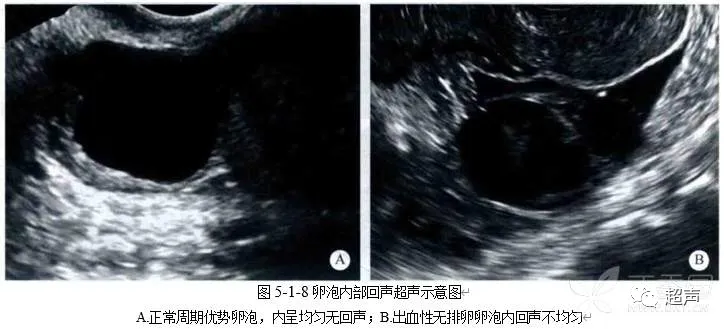

健康科普 | 好“孕”第一步——卵泡的超声监测